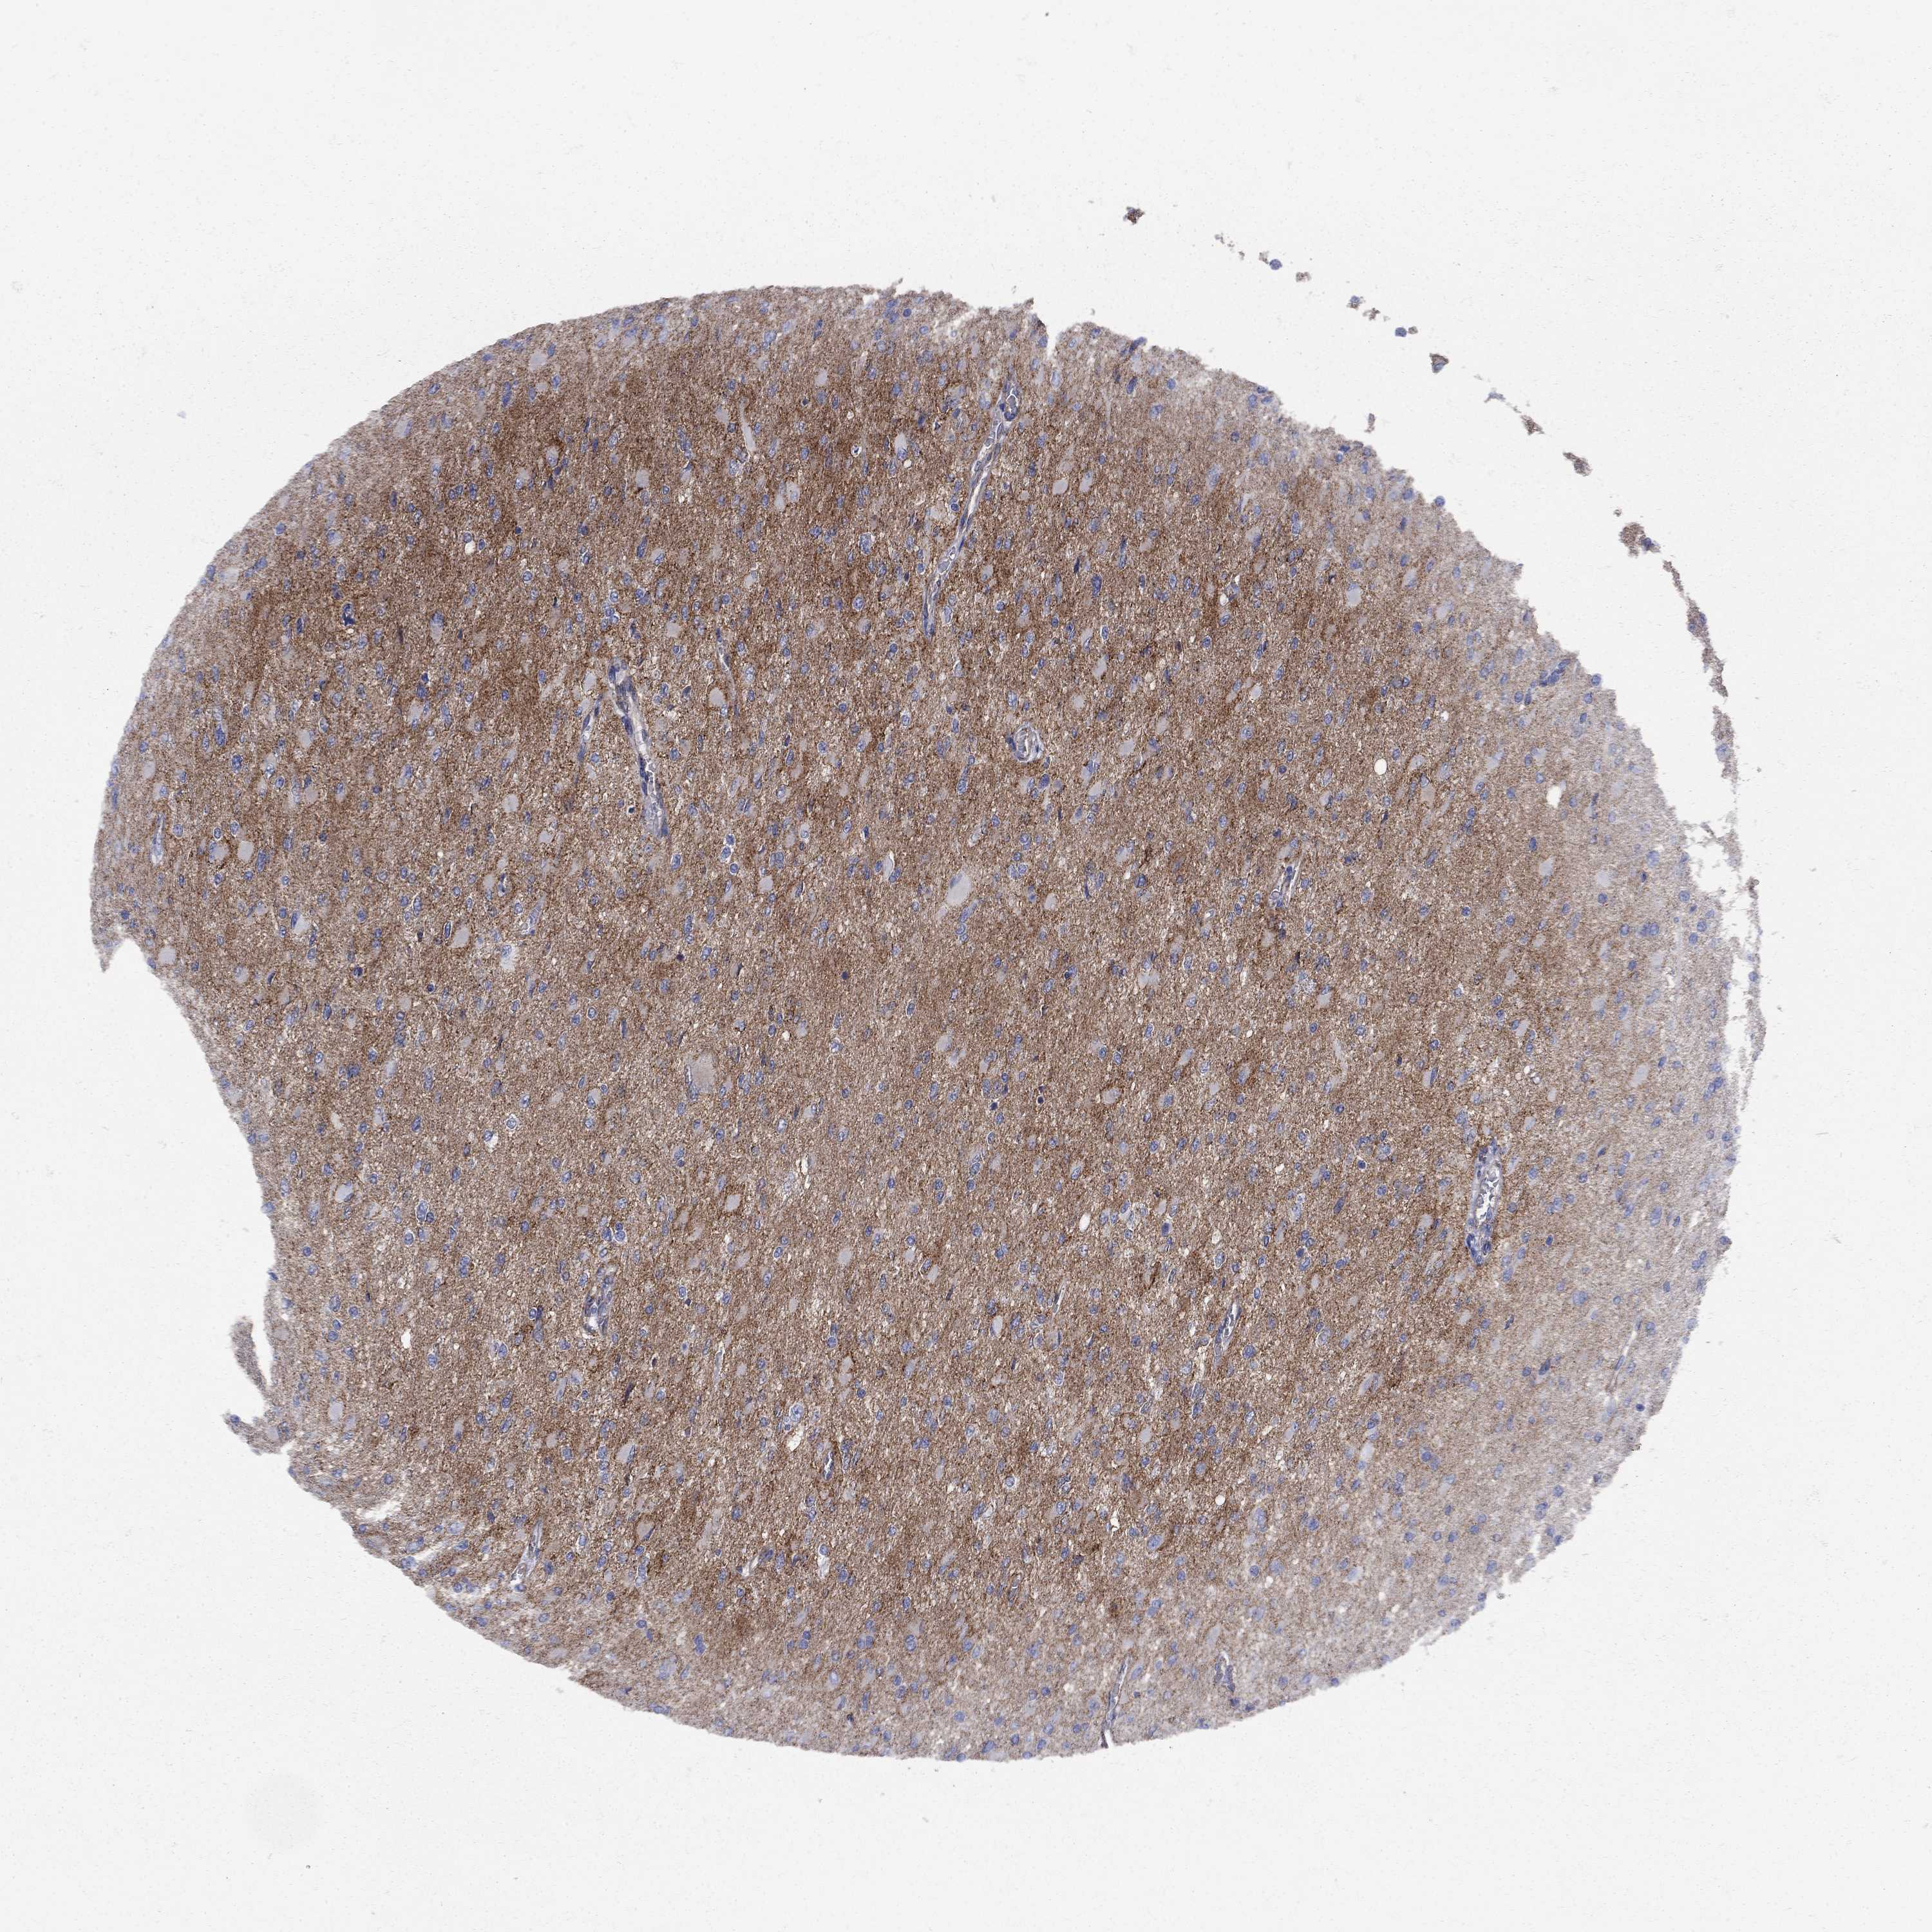

GLIOMA - Protein expressioni

A mouse-over function shows sample information and annotation data. Click on an image to view it in a full screen mode. Samples can be filtered based on level of antibody staining by selecting one or several of the following categories: high, medium, low and not detected. The assay and annotation is described here.

Note that samples used for immunohistochemistry by the Human Protein Atlas do not correspond to samples in the TCGA dataset.

Antibody stainingi

Antibody staining in the annotated cell types in the current human tissue is reported as not detected, low, medium, or high, based on conventional immunohistochemistry profiling in selected tissues. This score is based on the combination of the staining intensity and fraction of stained cells.

Each image is clickable and will lead to virtual microscopy that enables deeper exploration of all samples and also displays staining intensity scores, fraction scores and subcellular localization as well as patient and tissue information for each sample.

Antibody HPA005665

Antibody HPA036534

Glioma, malignant, High grade

Glioma, malignant, NOS

Glioma, malignant, Low grade